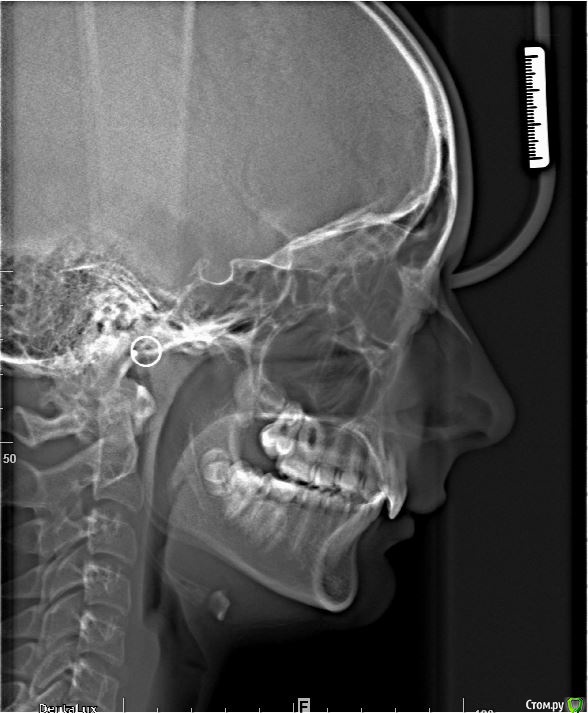

post-38874-0-87186300-1459536185_thumb.jpgpost-38874-0-15339500-1459536188_thumb.jpgpost-38874-0-82577500-1459536190_thumb.jpgpost-38874-0-61079300-1459536193_thumb.jpgpost-38874-0-22178300-1459536196_thumb.jpgpost-38874-0-56404400-1459536198_thumb.jpgpost-38874-0-43380300-1459536199_thumb.jpgpost-38874-0-04081600-1459536228_thumb.jpgpost-38874-0-34503200-1459536230_thumb.jpgpost-38874-0-34236500-1459536233_thumb.jpgpost-38874-0-95387400-1459536234_thumb.jpgpost-38874-0-86290600-1459536242_thumb.jpgpost-38874-0-47956700-1459536252_thumb.jpgpost-38874-0-98507600-1459536273_thumb.jpgpost-38874-0-52220700-1459536283_thumb.jpgpost-38874-0-12327700-1459536263_thumb.jpg

Извините за качество фото.

Пациентка 14 лет. Было принято решение лечить без удаления, тк. профиль не позволяет да и ретропозиция нч. Лечение идет. Я назначила ранние эластики слабые, на 17/25 нити на вч и 18 нити на нч. по 2 классу короткие 3,4-4,5. Пациентка пришла через месяц жалуется на щелканье челюсти во время ношения эластиков и сразу после их снятия. Т.е. если открывает рот, то челюсть скачкообразно двигается и щелчками. Последние 2 недели, когда много говорит, то вообще стала заедать. Это она так сказала. После отмены эластиков (страшно), через неделю пришла, рот открывает ровно, без девиации, щелчков нет. Вопрос: почему щелкает и что с этим делать? По поводу прикуса, посоветуйте, пожалуйста, как нормализовать? Аппарат типа гербста? может ей твинблок сделать? Эластики? К сожалению другими методами я пока что не владею. Спасибо, очень жду ваших советов.

Конечно, через интеонет трудно ответить, ведь щелчки бывают разные (в начале фазы открывания, в конце, в начале фазы закрывания, в конце закрывания? То есть если у нее смещена головка кзади ппи щакрытом рте, то при открывании у нее сразу должен быть щелчок (головка догнала диск), пожевала .., потом во время закрытия в самом конце опять щелчок (головка съехала с диска и стала в свое привычное положение). Это обычная картина при втором классе. Несьемные аппараты не будут давать уходить челюсти назад, щелчков быть не должно. После снятия аппарата зафиксируете новое положение челюсти бугорками антагонистов